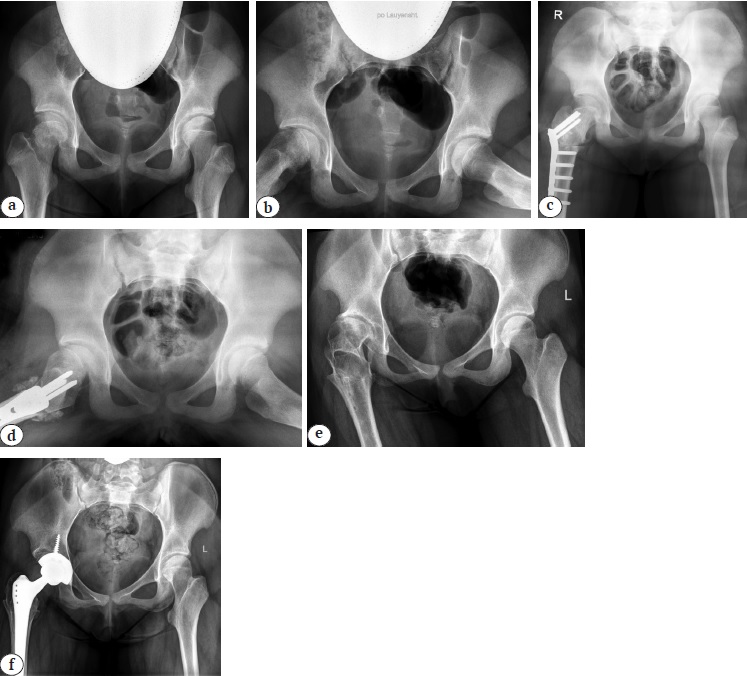

В результате этих вмешательств в подавляющем большинстве случаев развивались грубые деформации как со стороны проксимального отдела бедренной кости, вплоть до его тотального лизиса, так и со стороны вертлужной впадины. На наш взгляд, для описания подобного рентгеноанатомического строения тазобедренного сустава более уместным термином являлся бы диартроз или сочленение. Кроме того, в результате проведения многократных хирургических операций у всех пациентов отмечалось массивное рубцовое перерождение мышц области тазобедренного сустава и выраженное укорочение нижней конечности за счет бедренной кости (рис. 4).

Рис. 4. История хирургических вмешательств у пациентки 14 лет: а — рентгенограмма тазобедренных суставов на момент первичного обращения к специалисту в возрасте 1 г. 7 мес. (дисплазия левого тазобедренного сустава IV–1 степени по дополненной классификации D. Tönnis [16]); b — ближайший результат хирургической реконструкции левого тазобедренного сустава (релюксация с выраженными дистрофическими явлениями в проксимальном отделе бедренной кости); c — повторная попытка стабилизации левого тазобедренного сустава (отсутствие концентрического вправления головки бедренной кости в вертлужную впадину, высокое положение большого вертела, мальпозиция металлоконструкций в виде их пенетрации в полость сустава); d, e — отдаленный результат хирургического лечения (тотальный лизис проксимального отдела бедренной кости, вертлужная впадина как анатомическая структура отсутствует, укорочение бедренной кости более 8 см, экстремально малые размеры канала бедренной кости и локации для имплантации чашки эндопротеза в анатомическую позицию); f — среднесрочный результат выполнения тотального бесцементного эндопротезирования системой Zimmer Biomet (чашка TMT® 38 мм; ножка Wagner cone® 13, пара трения: металл — поперечносвязанный полиэтилен) с применением техник остеотомии большого вертела по T. Paavilainen и дилятационной остеотомии бедренной кости

Fig. 4. Surgical interventions sequence of a 14-year-old patient: а — X-ray of the hip joints at the initial specialist visit at the age of 1 year and 7 months (grade IV-1 left-sided hip dysplasia according to the supplemented D. Tönnis classification [16]); b — short-term result of the left hip joint surgical reconstruction (reluxation with pronounced dystrophic changes in the proximal femur); с — a repeated attempt to stabilize the left hip joint (absence of concentric reduction of the femoral head into the acetabulum, a high position of the large trochanter, malposition of metal structures in the form of their penetration into the joint cavity); d, e — long-term result of the surgical treatment (total lysis of the proximal femur, acetabulum as an anatomical structure is absent, shortening of the femur bone over 8 cm, extremely small sizes of the femoral canal and the location for endoprosthesis cup implantation in the anatomical position); f — mid-term result of cementless THA performed with the Zimmer Biomet system (TMT® 38 mm cup; Wagner cone® 13, metal-crosslinked polyethylene), the T. Paavilainen techniques of greater trochanter osteotomy and dilated osteotomy of the femur